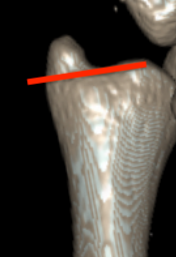

Classification ulna styloid fractures

| Type 1: Tip | Type 2: Base | Type 3: Proximal to styloid |

Operative management

Indication

DRUJ instability after distal radius ORIF with ulna styloid fracture

Techniques

Options

Styloid screw

Tension band wire

Ulna hook plate

Synthes distal ulna hook plate

AO surgery ulna styloid fracture screw fixation

AO surgery ulna styloid TBW fixation